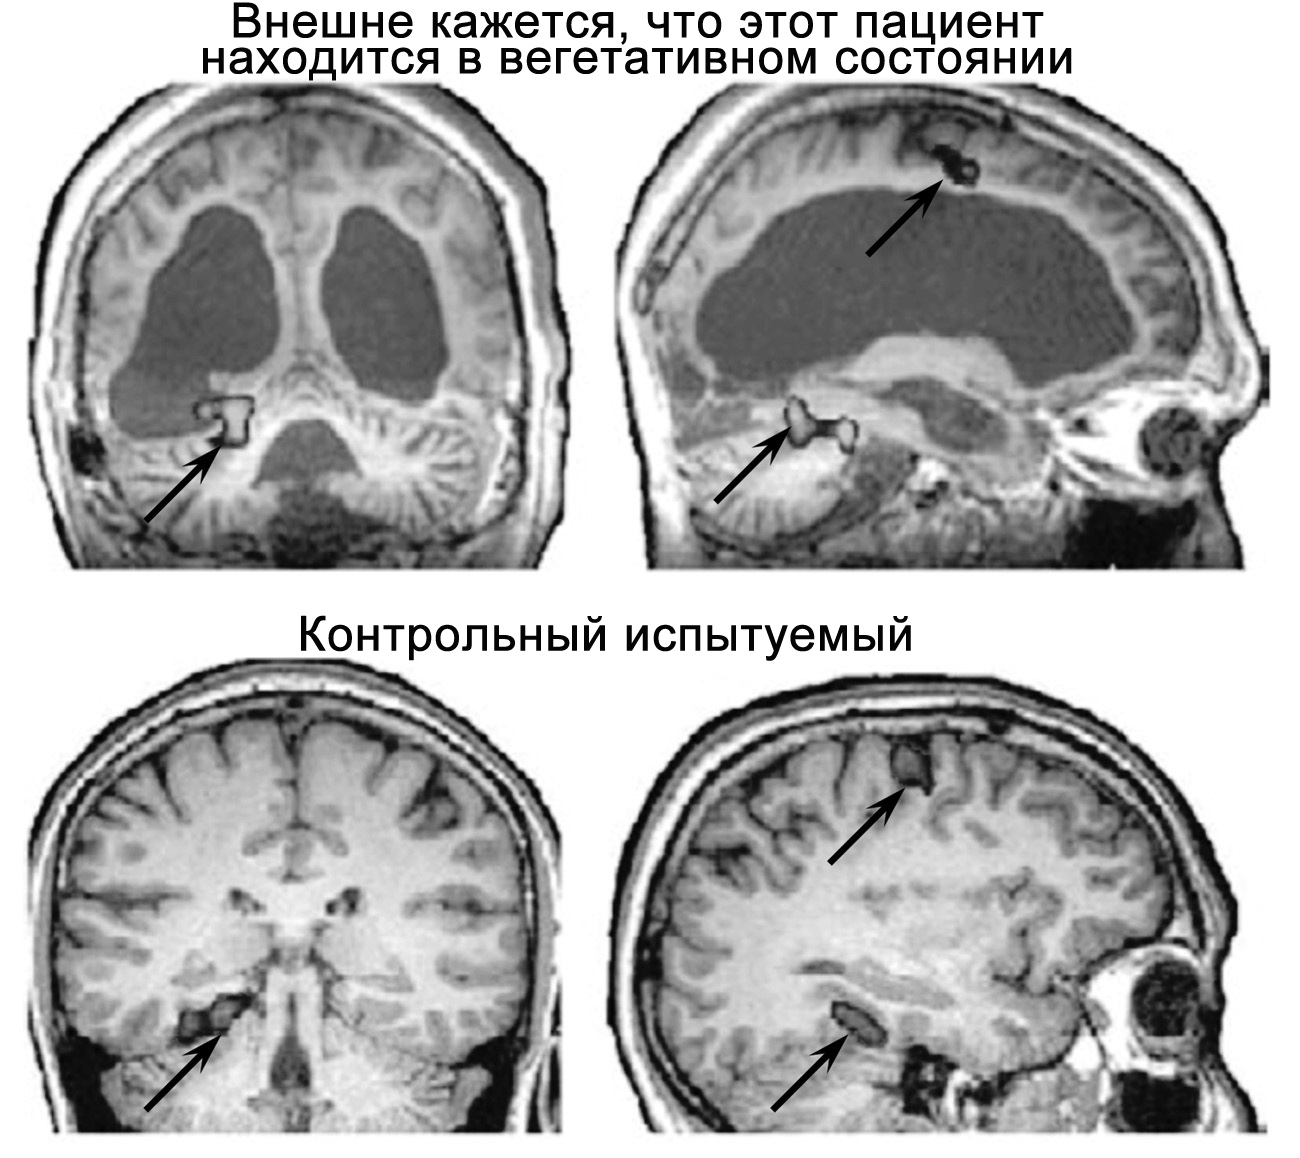

Рисунок 30. Некоторые пациенты, внешне демонстрирующие признаки вегетативного состояния, при выполнении сложных умственных задач показывают практически нормальную активность мозга, а следовательно, можно предположить, что они находятся в сознании. Пациент в верхней части рисунка не мог ни двигаться, ни говорить, однако корректно отвечал на заданные ему вопросы, активизируя для этого различные участки мозга. Чтобы ответить «нет», он должен был представить, будто входит к себе в квартиру, а «да» — вообразить, что играет в теннис. Когда пациента спросили, звали ли его отца Томас, участки мозга, отвечающие за пространственное ориентирование, активировались так же, как у здорового человека, то есть ответ (соответствующий действительности) был «нет». При этом пациент не демонстрировал никаких признаков способности к коммуникации, а также признаков сознания, и потому считалось, что он пребывает в вегетативном состоянии. На снимке хорошо видны имеющиеся у него обширные поражения мозга